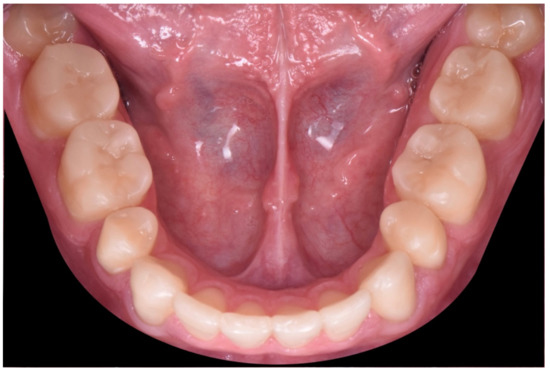

2. Clinical Report

2.1. Planning Phase

2.2. Restorative Phase